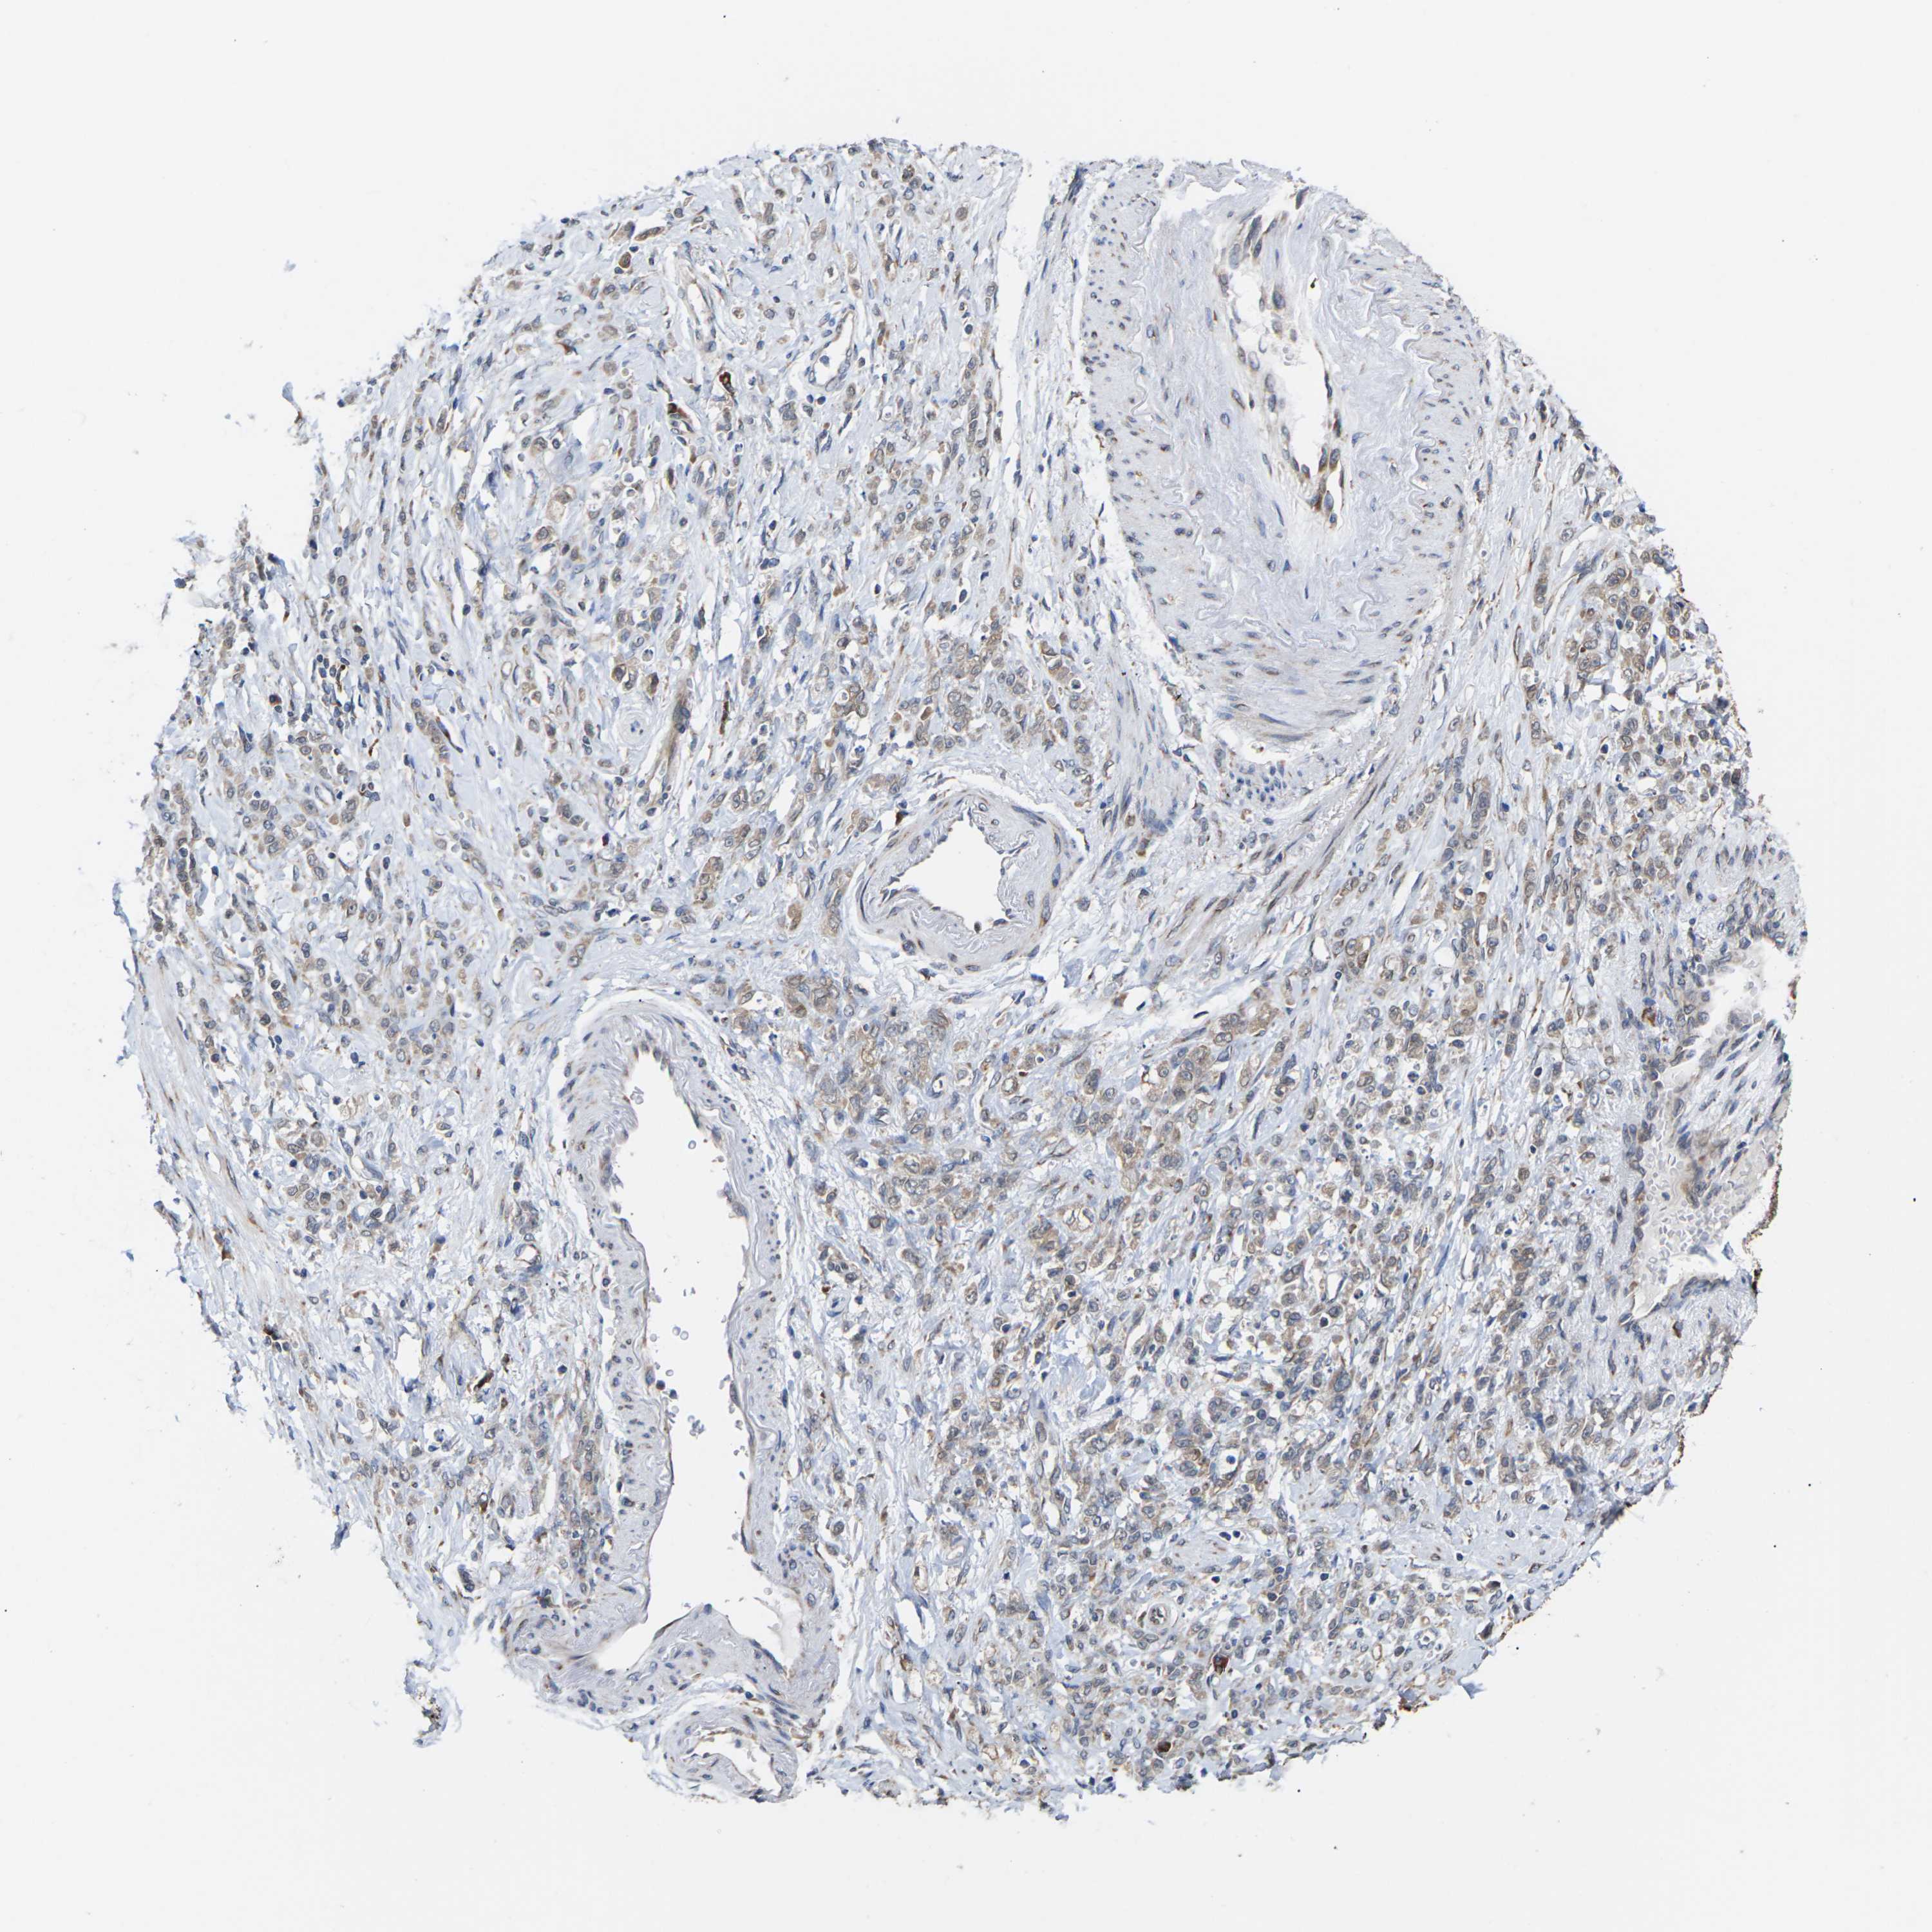

STOMACH CANCER - Protein expressioni

A mouse-over function shows sample information and annotation data. Click on an image to view it in a full screen mode. Samples can be filtered based on level of antibody staining by selecting one or several of the following categories: high, medium, low and not detected. The assay and annotation is described here.

Note that samples used for immunohistochemistry by the Human Protein Atlas do not correspond to samples in the TCGA dataset.

Antibody stainingi

Antibody staining in the annotated cell types in the current human tissue is reported as not detected, low, medium, or high, based on conventional immunohistochemistry profiling in selected tissues. This score is based on the combination of the staining intensity and fraction of stained cells.

Each image is clickable and will lead to virtual microscopy that enables deeper exploration of all samples and also displays staining intensity scores, fraction scores and subcellular localization as well as patient and tissue information for each sample.

Antibody HPA014907

Staining

High

Medium

Low

Not detected

Intensity

Strong

Moderate

Weak

Negative

Quantity

>75%

75%-25%

<25%

None

Location

Nuclear

Cytoplasmic/membranous

Cytoplasmic/membranous,nuclear

Adenocarcinoma, NOS

Adenocarcinoma, High grade